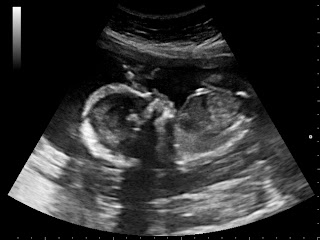

JT says it's only fair if it's a girl. Well, this morning we found out that, in this case anyway, all's fair. :)